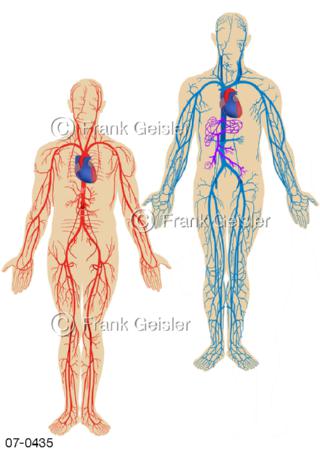

Bildergalerie Herz, Blutkreislauf

Bilder zu Herz, ein muskuläres Hohlorgan, das den menschlichen Körper durch rhythmische Kontraktionen mit Blut versorgt und dadurch die Durchblutung der Organe sichert, das Kreislaufsystem zeigt den Transport von arteriellem sowie venösem Blut durch das kardiovaskuläre System (Herz-Kreislauf-System), bestehend aus Blutgefäßen, Lymphgefäßen und dem Herz